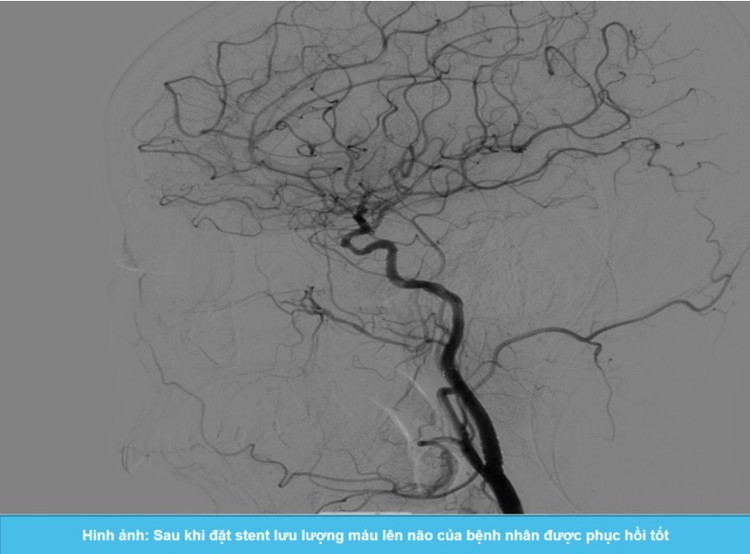

Dưới sự hỗ trợ của hệ thống chụp mạch số hóa xóa nền DSA, ThS.BS Giáp Hùng Mạnh cùng ê-kíp can thiệp đã tiến hành nong động mạch cảnh trong bên trái bị hẹp và đặt stent thành công, giúp mở rộng lòng mạch hiệu quả, phục hồi lưu lượng máu lên não cho bệnh nhân.

Sau can thiệp, bệnh nhân phục hồi tốt, các triệu chứng thần kinh cải thiện rõ rệt, tỉnh táo, không có biến chứng sau thủ thuật.